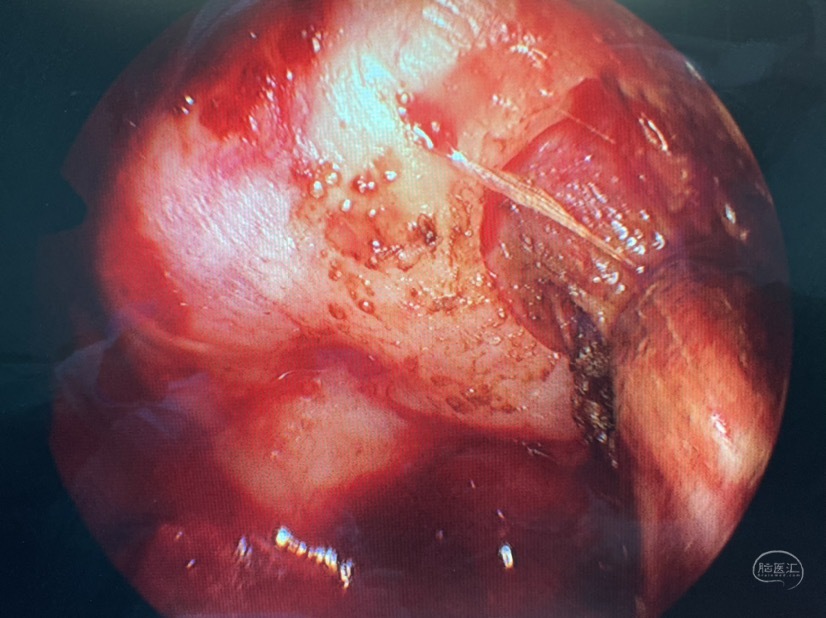

术中证实为蝶窦外侧隐窝的脑膜脑膨出

切除部分膨出脑组织,外侧隐窝因翼突根部的遮挡操作受限